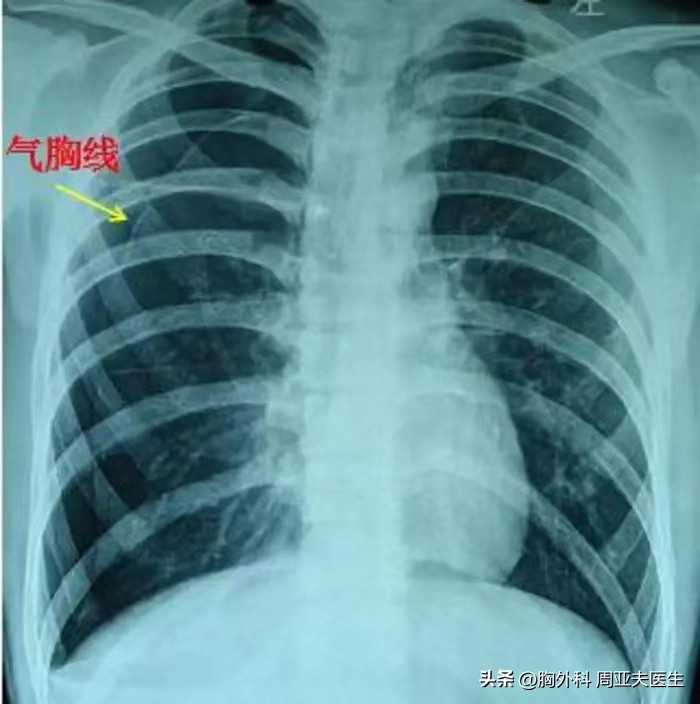

所谓的气胸线,就是肺压缩后的肺边界,正常的非边界与胸壁是重叠的